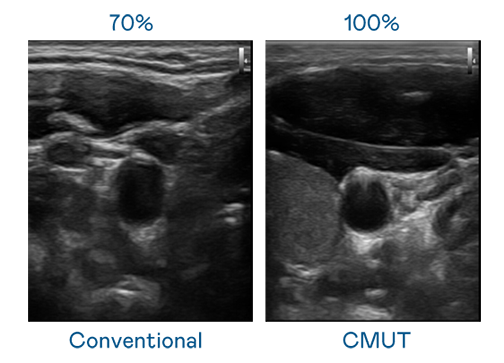

CMUT 技术是一种用电容式微机电元件来产生超音波讯号的技术。与传统 PZT 压电式技术相比,CMUT 频宽增加 30%,更宽频的超音波讯号让影像解析度大幅提升,是实现高影像品质医疗超音波扫描、促进精准医疗发展的关键技术。

大频宽带来超清晰影像

超音波影像的解析度高低,首先取决于探头能发出的讯号频宽。极速快3 CMUT 可提供高清晰的超音波讯号,提供高频宽、高灵敏度、影像纹理细节更高的超音波影像,协助医护人员缩短影像判读时间及利用精准的医疗影像进行诊断。